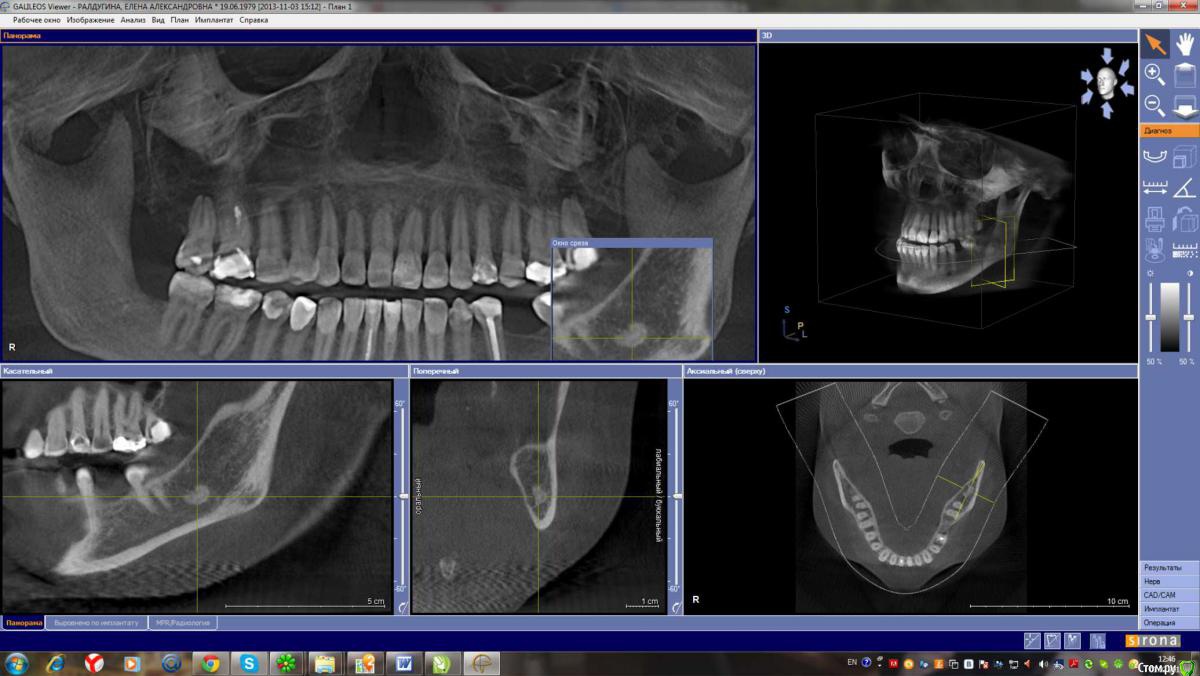

Лена35 Опубликовано 1 февраля, 2015 Автор Поделиться Опубликовано 1 февраля, 2015 кт апрель 2013кт ноябрь 2013последнее кт 2014Удаление сложное было? Не могу прицелиться, чтобы верхний корень было хорошо видно, но он там - в клинике с докторами мы смотрели его, он прямо в десну упирается и жжет там, но не воспаляется, не опухает, не гноится. Может потому что я на нвпс периодически сижу. Или дело вообще не в этих штуках? А как сказали артролог и невролог = миофасцеальный болевой синдром, триггерные точки, повреждение связок при вправлении вывиха... Но почему боль чаще сего я чувствую в области этого верхнего корня? И как долго еще это все будет болеть? Буду благодарна вашим обнадеживающим ответам. Заранее спасибо. Именно от боли острой в этой зоне я мучаюсь после вывиха более четырех месяцев. А до этого в этой зоне я чувствовала периодически , как будто зуб растет и думала, что фантомные боли, я только в сентябре узнала, что эти штуки у меня там есть. Операцию делать не хочу, боюсь осложнений. Но если боль от этого, то жить так тоже не хочу. И как делать операцию, если у меня открытие рта 2,5 см? Ссылка на комментарий

Alejandro Опубликовано 1 февраля, 2015 Поделиться Опубликовано 1 февраля, 2015 Я бы начал с удаления 27-го зуба, далее необходимо разобраться с лимфаденитом (если он ещё будет в стадии обострения). Образование в области нижнечелюстного канала очень похоже на один из корней 38 зуба, я бы предложил его удалить. А открывание рта как давно ограничено? Ссылка на комментарий

Alejandro Опубликовано 2 февраля, 2015 Поделиться Опубликовано 2 февраля, 2015 как Вы по КТ увидели лимфоденит? Выдернуть 27 мне еще никто не предлагал. Поначалу зубы лечатся вроде как эндодонтически.... Про лимфаденит Вы в 26 посте сами сообщили. Сделайте скрин среза в области 27-го, там не очень всё хорошо на верхушках корней. И, кстати, случаи когда зубы приходится удалять без эндодонтии не так уж и редки, к сожалению... Ссылка на комментарий